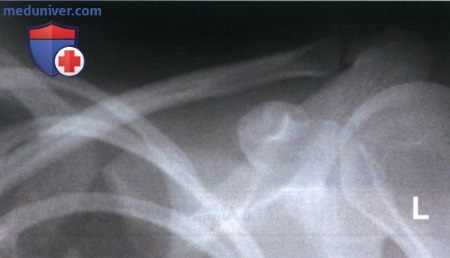

Пример анализа рентгенограмм ключицы в ПЗ проекции

а) Рентгенограмма 1:

1. Анализ. Медиальный конец ключицы отодвинут от латерального края позвоночного столба. Туловище было повернуто в сторону исследуемого плечевого сустава.

2. Коррекция. Поверните туловище в противоположную сторону так, чтобы плечевые суставы располагались на равном расстоянии от ПИ.

б) Рентгенограмма 2:

1. Анализ. Верхний угол лопатки проецируется выше середины ключицы. Верх срединной коронарной плоскости был наклонен вперед.

2. Коррекция. Выпрямите верхнегрудной отдел позвоночника так, чтобы срединная коронарная плоскость располагалась параллельно ПИ.

в) Рентгенограмма 3:

1. Анализ. Верхний угол лопатки проецируется ниже середины ключицы. Верх срединной коронарной плоскости был наклонен назад. Медиальный конец ключицы не входит в экспозиционное поле. ЦЛ был направлен издишне латерально.

2. Коррекция. Выпрямите верхнегрудной отдел позвоночника так, чтобы срединная коронарная плоскость располагалась параллельно ПИ. Направьте ЦЛ медиальнее приблизительно на 2,5 см. Отколлимируйте экспозиционное поле так, чтобы в него вошел медиальный конец ключицы.